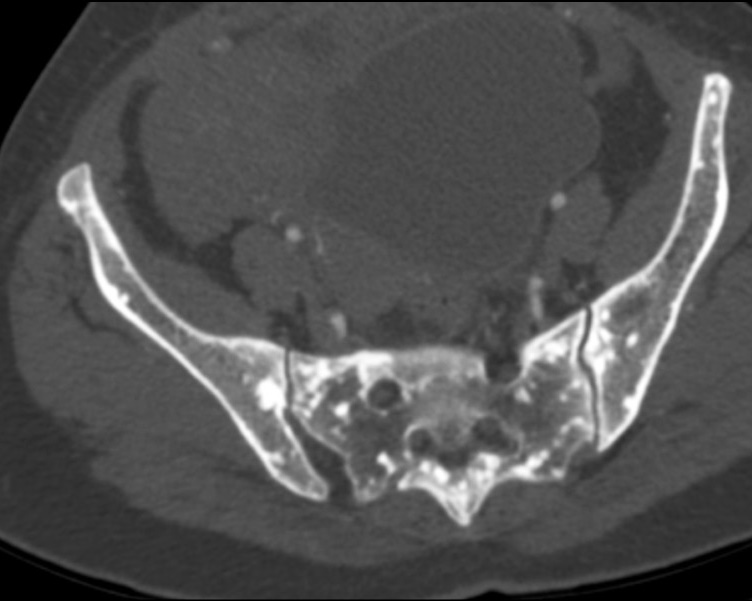

Osteopoikilosis in the ribs, pelvic region and spine: a case report

Resumo

Osteopoikilosis is a rare inherited benign bone dysplasia incidentally found on radiological exams. It is characterized by a specific radiological pattern: diffuse, round or oval, symmetrically shaped sclerotic bone areas distributed throughout the skeleton. It is essential to do a correct diagnosis because these lesions could be easily confused with bone metastasis.

We reported a case of an osteopoikilosis patient presenting to our clinic with transient loss of consciousness and without any numbness, tingling and weakness in the legs or other parts of the body. The computed tomography scan showed multiple small sclerotic foci bone islands, scattered throughout the thoracic and lumbar spine, ribs, pelvic bone, sacrum and bilateral proximal femur. No significant increase in the activity was detected in technetium-99m whole-body bone scintigraphy. The patient was diagnosed with characteristic radiological findings of osteopoikilosis and was followed up.

481-487